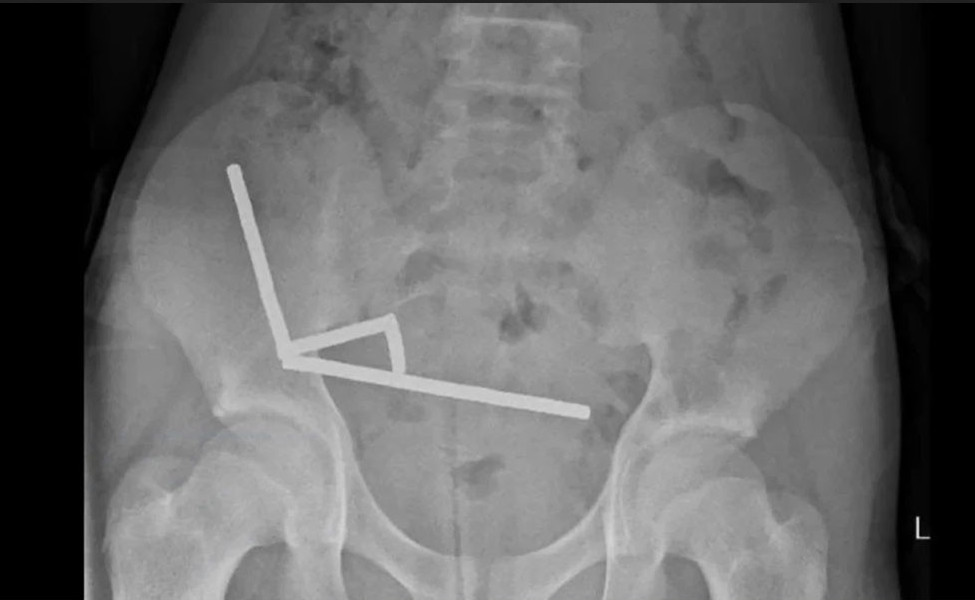

প্রতিবেদনে বলা হয়েছে, চার দিন ধরে পেটে তীব্র ব্যথা নিয়ে কিশোরটিকে নর্থ আইল্যান্ডের টরাঙ্গা হাসপাতালে ভর্তি করা হয়। নিউজিল্যান্ড মেডিকেল জার্নালে প্রকাশিত হাসপাতালের চিকিৎসকদের প্রতিবেদন অনুযায়ী, কিশোরটি ভর্তির প্রায় এক সপ্তাহ আগে প্রায় ৮০ থেকে ১০০টি (৫ী২ মিলিমিটার আকারের) শক্তিশালী নিওডিমিয়াম চুম্বক গিলে ফেলেছিল। এক্স-রে রিপোর্টে দেখা যায়, এই চুম্বকগুলো তার অন্ত্রের ভেতরে চারটি সরলরেখায় জড়ো হয়েছে। চিকিৎসকেরা জানান, চুম্বকীয় শক্তির কারণে অন্ত্রের বিভিন্ন অংশ একসঙ্গে আটকে যাওয়ায় তীব্র চাপ সৃষ্টি হয়, যার ফলে টিস্যু মারা যায়।